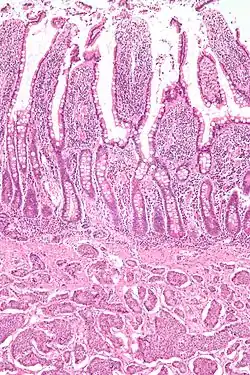

Micrograph of a neuroendocrine tumor. H&E stain.

Small intestinal neuroendocrine tumor at bottom third of image, showing the typical intramural (within the wall) location, and overlying intact epithelium. H&E stain.

NETs are often small, yellow or tan masses, often located in the submucosa or more deeply intramurally, and they can be very firm due to an accompanying intense desmoplastic reaction. The overlying mucosa may be either intact or ulcerated. Some GEP-NETs invade deeply to involve the mesentery.[72] Histologically, NETs are an example of "small blue cell tumors," showing uniform cells which have a round to oval stippled nucleus and scant, pink granular cytoplasm. The cells may align variously in islands, glands or sheets. High power examination shows bland cytopathology. Electron microscopy can identify secretory granules. There is usually minimal pleomorphism but less commonly there can be anaplasia, mitotic activity, and necrosis.